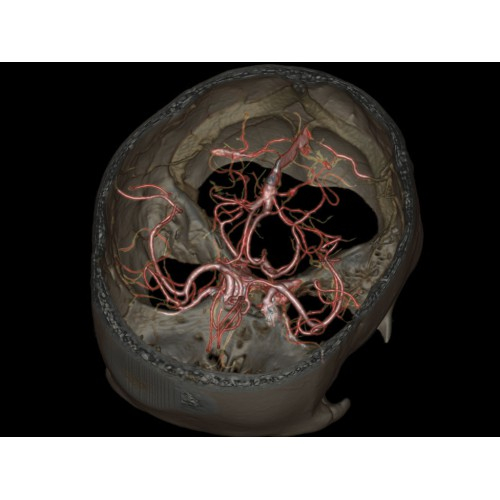

Позволяет проводить комплексные исследования всех анатомических зон, включая нейровизуализацию, ангиографию, исследования органов грудной и брюшной полости. Особенно эффективен для раннего выявления онкологических заболеваний.